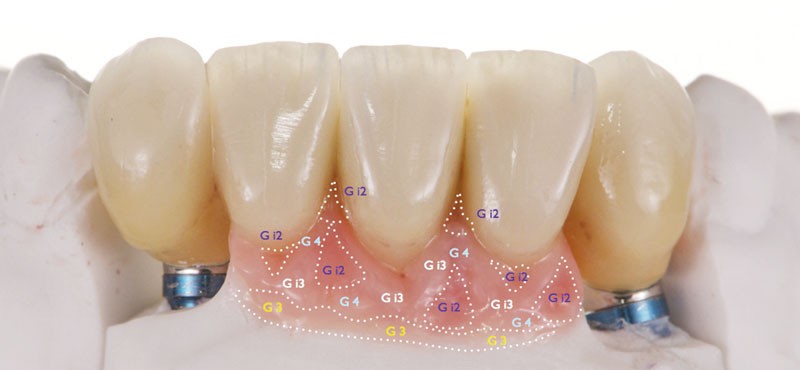

Cette étape valide la passivité de l’armature avant de procéder au montage de la céramique. Pour relever la couleur de la fausse gencive, nous utilisons le nuancier « gingiva solution » (Ivoclar-Vivadent) (fig. 4a).

Pour personnaliser les témoins de saturation différente, nous employons le moule Smile-Line (fig. 4b). La figure 4c présente…